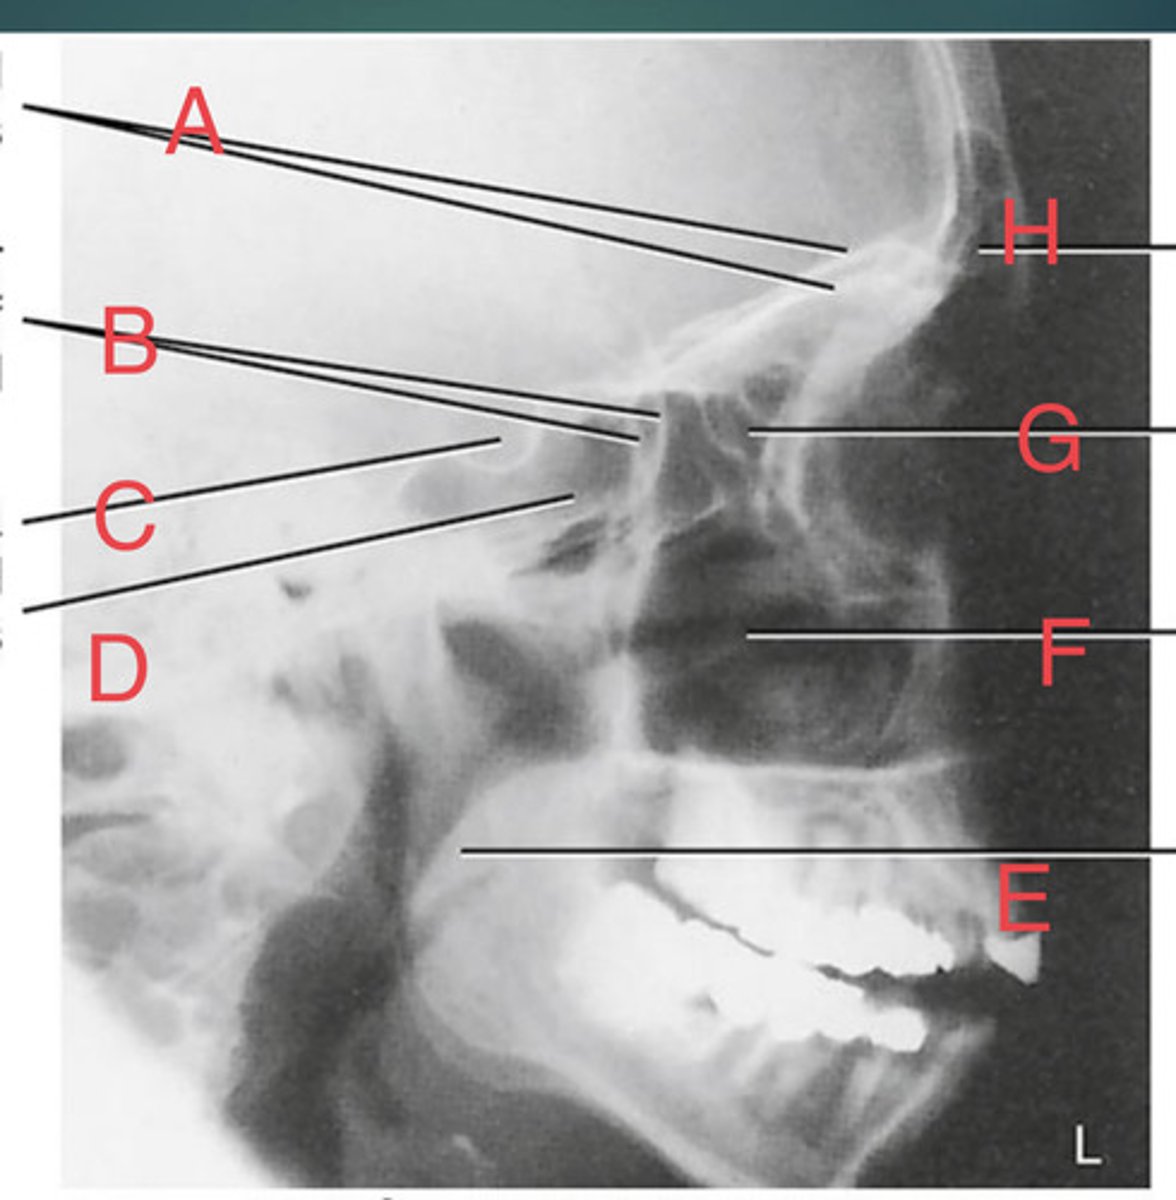

Lateral sinus

What position?

L. Orbital roofs

A.

L. Greater wings of sphenoid

B.

sella turcica of sphenoid

C.

L. Sphenoid sinus

D.

L. Rami of mandible

E.

L. Maxillary sinuses

F.

L. Ethmoid sinuses

G.

L. Frontal sinuses of frontal bone

H.